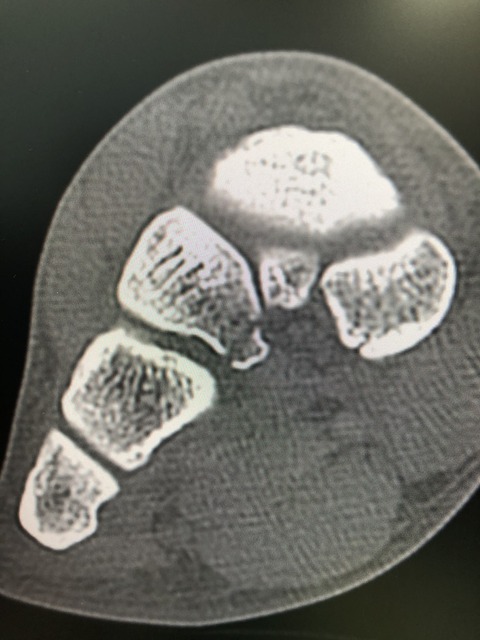

またまた、怪我

CTにて ヒビ入ってました

トレーナー、監督と話してテーピングして出場させました